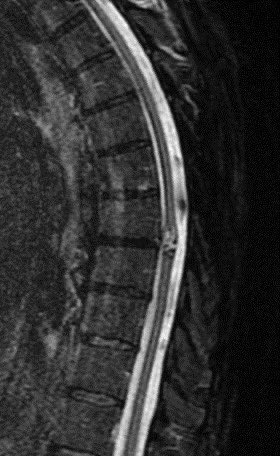

What is the most likely diagnosis in this 65 y/o M presenting w/ leg weakness, hyperreflexia, spasticity and absent vibration sense in the LE? #neu